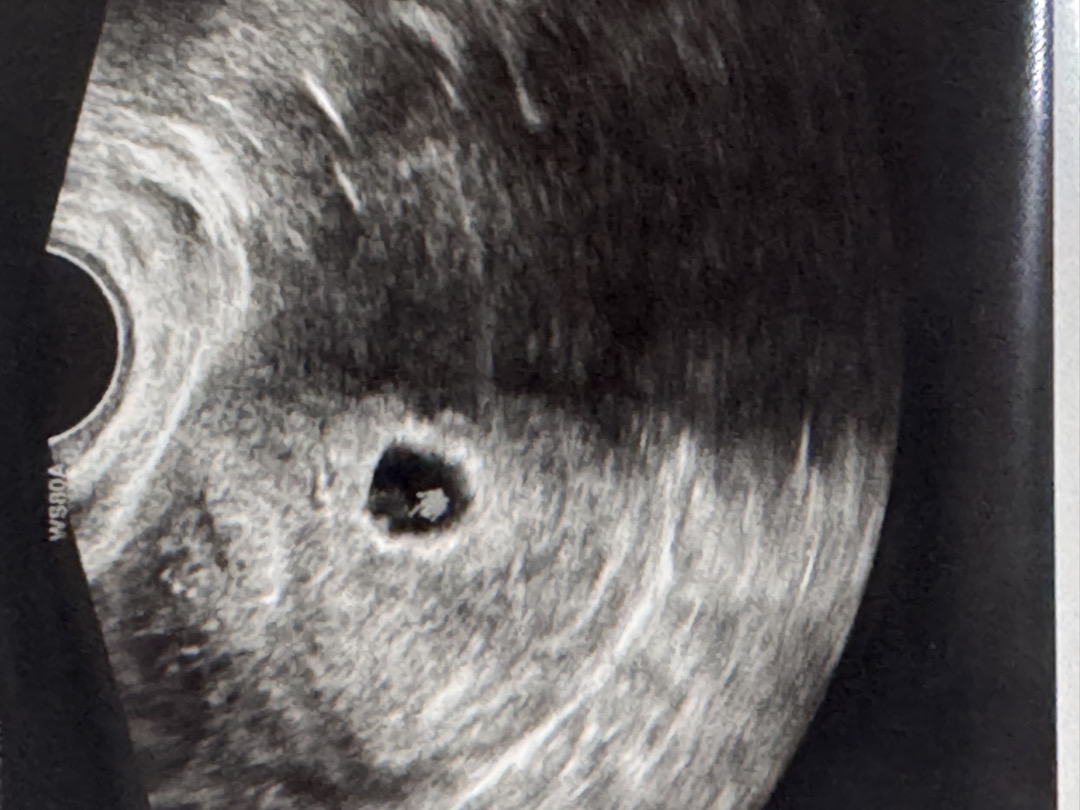

난황 크기 봐주세용 ㅠㅠ

6주차1일이도 아기집은 1.64cm로 정상이고 난황보고 왔어요..! 의사선생님은 아무 말씀 안하시고 잘크고있다고 담주에 보자고 하셨는데 사진 보니 난황이 큰 편 같아서요ㅠ 어떤가요..